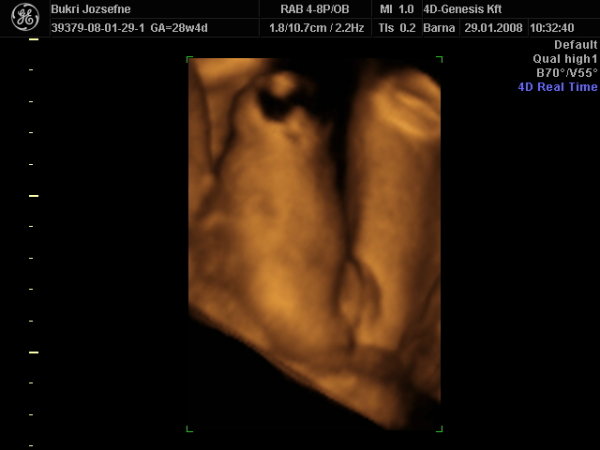

És egy tappancs 2008.03.08 19:45